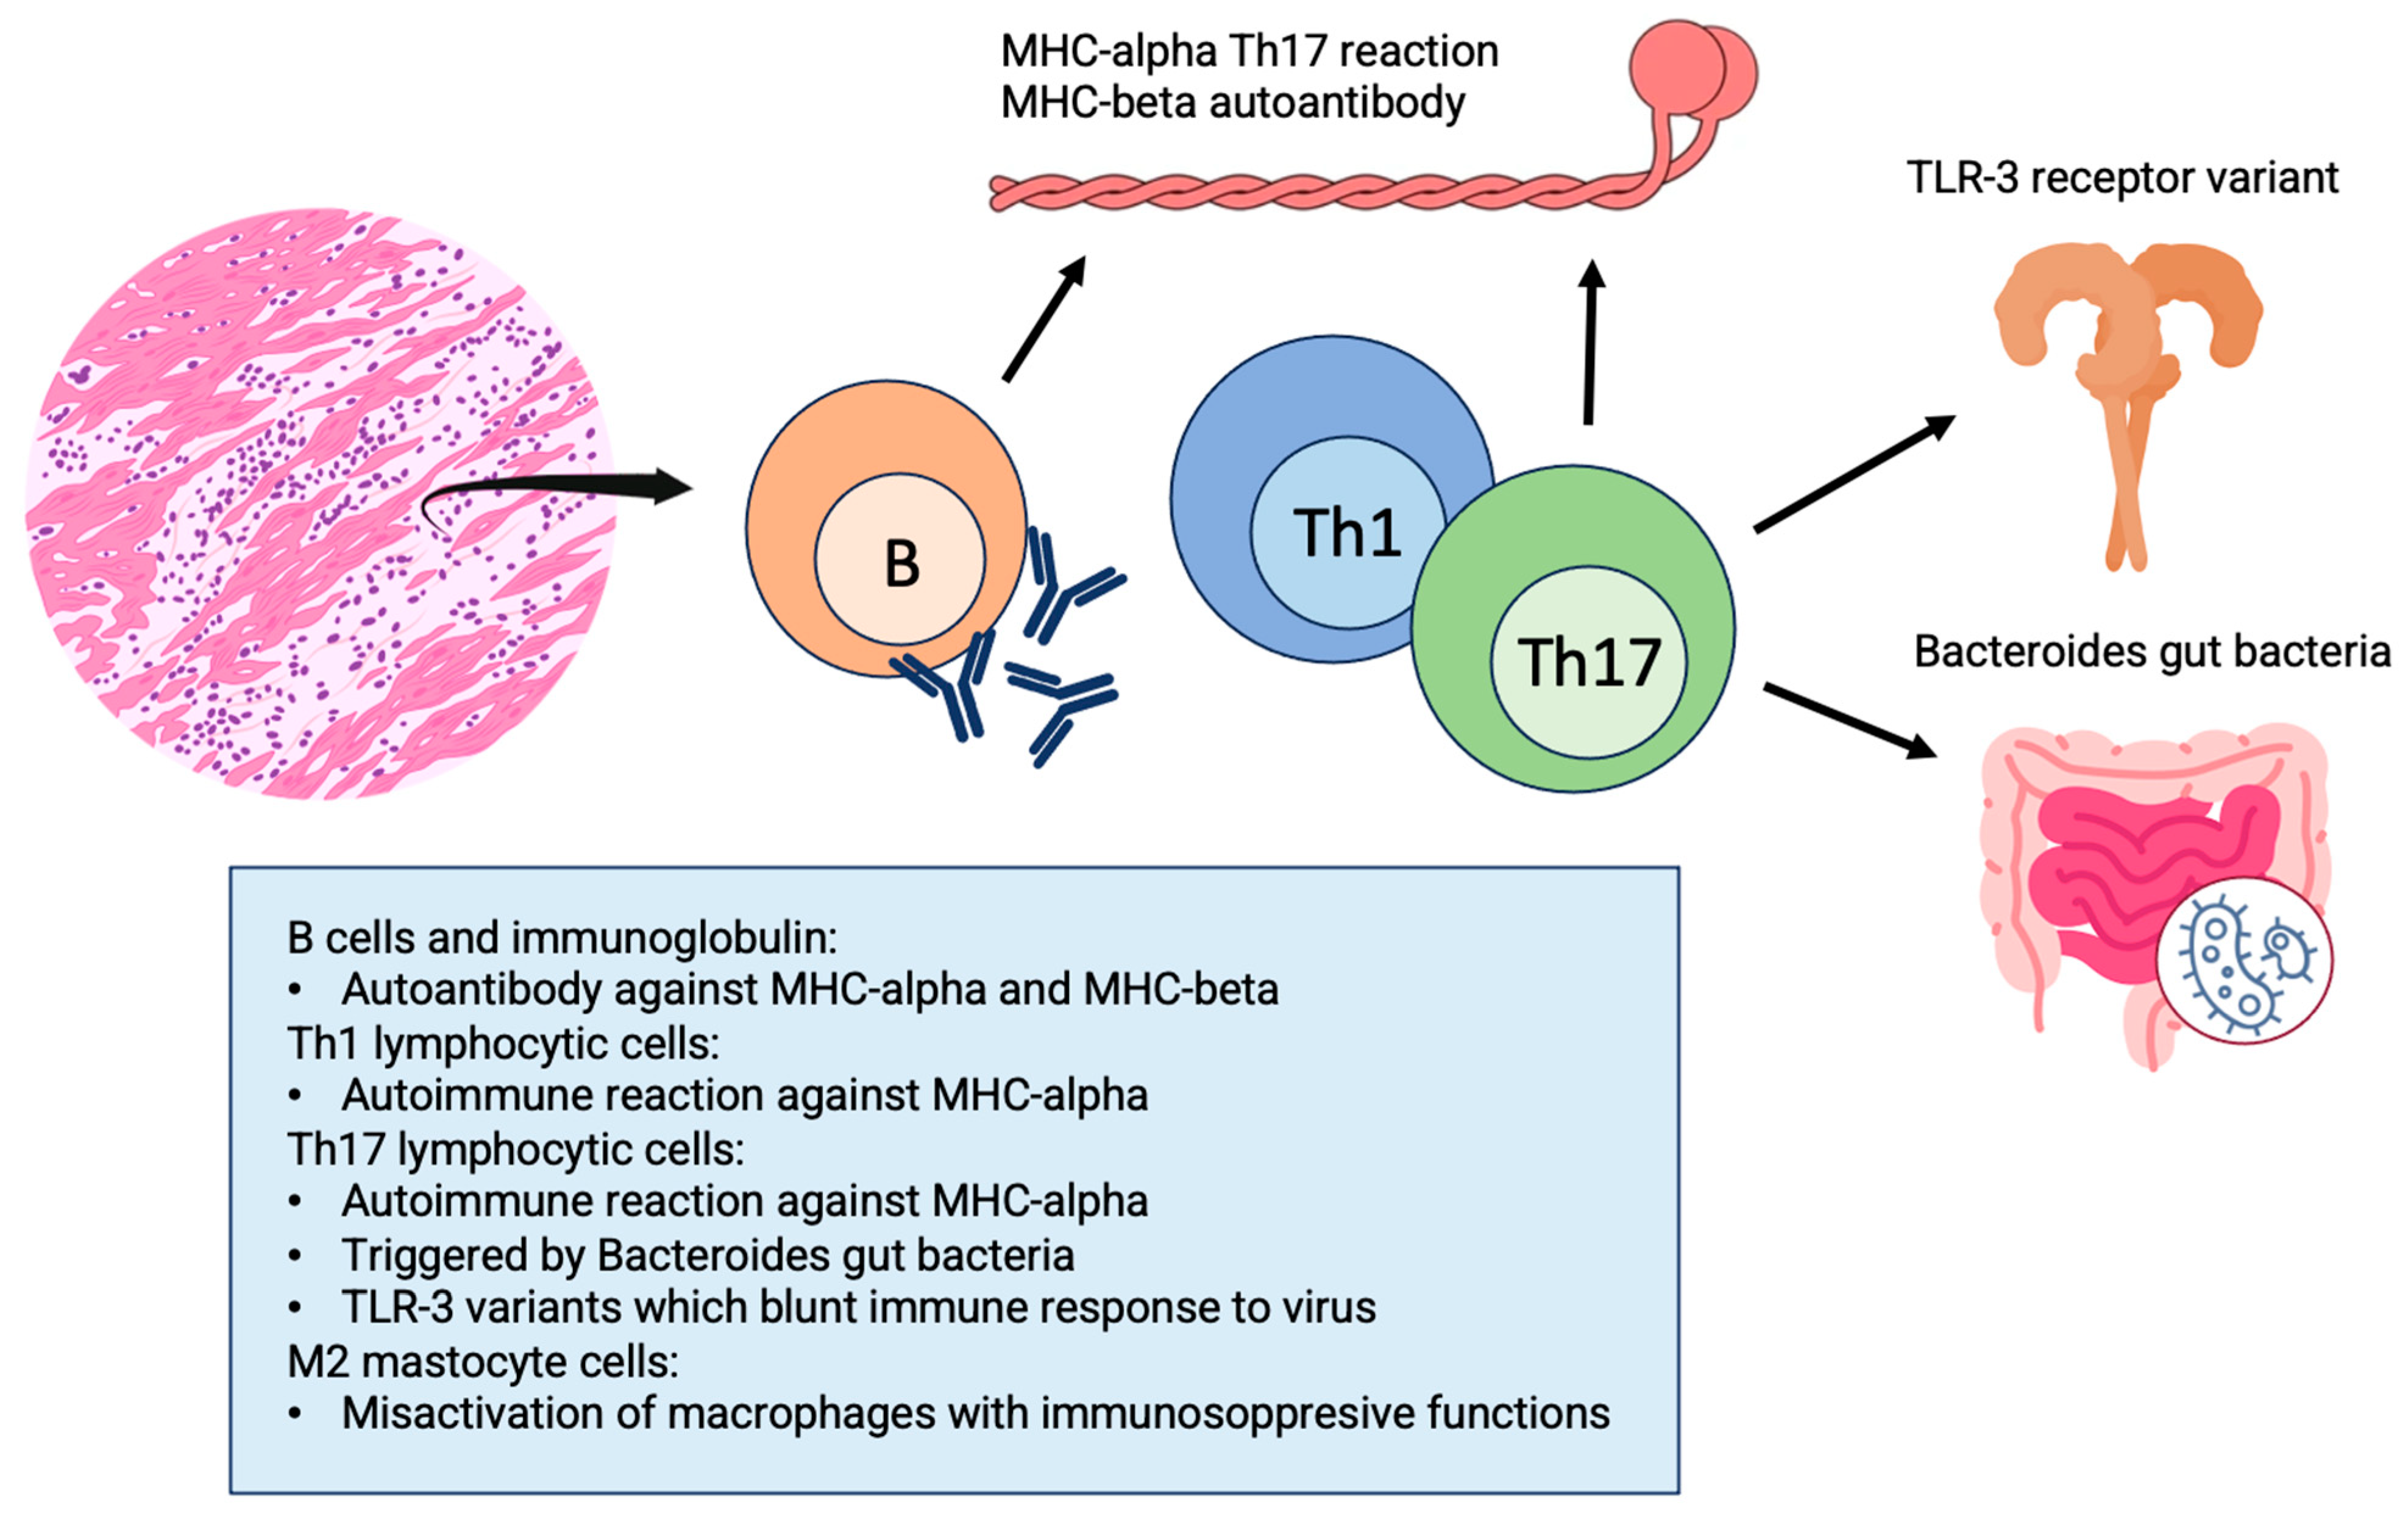

2.2. Pathophysiology

3.1. Etiology and Pathophysiology of Chronic infl-CMP Secondary to Acute Myocarditis